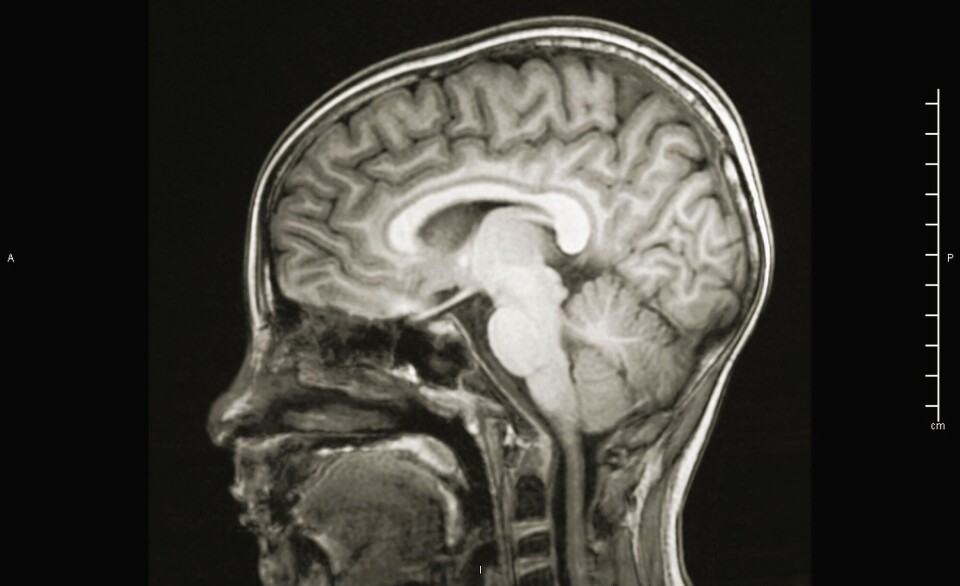

Participants in the new study had a contrast agent injected into their spinal cords, where it mixed with the clear cerebrospinal fluid.

This fluid flows up to the skull, surrounds the brain, and fills the cavities.

Two to three hours after the contrast agent was injected into the spine, it lit up in a very special way on the MRI images.

The fresh cerebrospinal fluid formed a doughnut-shaped ring around the large arteries entering the brain.

“It's difficult to explain this away, because we can see it with the naked eye. We see that cerebrospinal fluid moves along the blood vessels in the same direction as the blood, in the direction of the brain,” Eide explains.